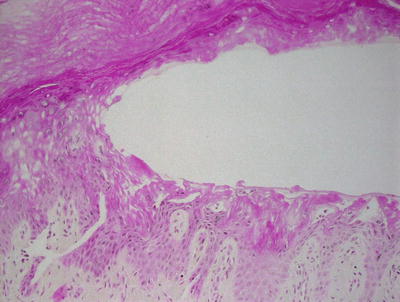

3.3.2 Histology

Histologic changes consist of a non-inflammatory subcorneal blister at the level of the granular layer (Fig. 3.7). In many cases, the stratum corneum, which is the blister roof, is desquamated and not present in the biopsy specimen. Its absence is often overlooked, making the diagnosis difficult. Rare acantholytic cells may be observed within the granular layer (Fig. 3.8). There is virtually no underlying inflammation within the dermis. Special stains for bacteria are negative [15].

Fig. 3.7

Staphylococcal scalded skin syndrome features a subcorneal blister in the absence of any inflammatory infiltrate